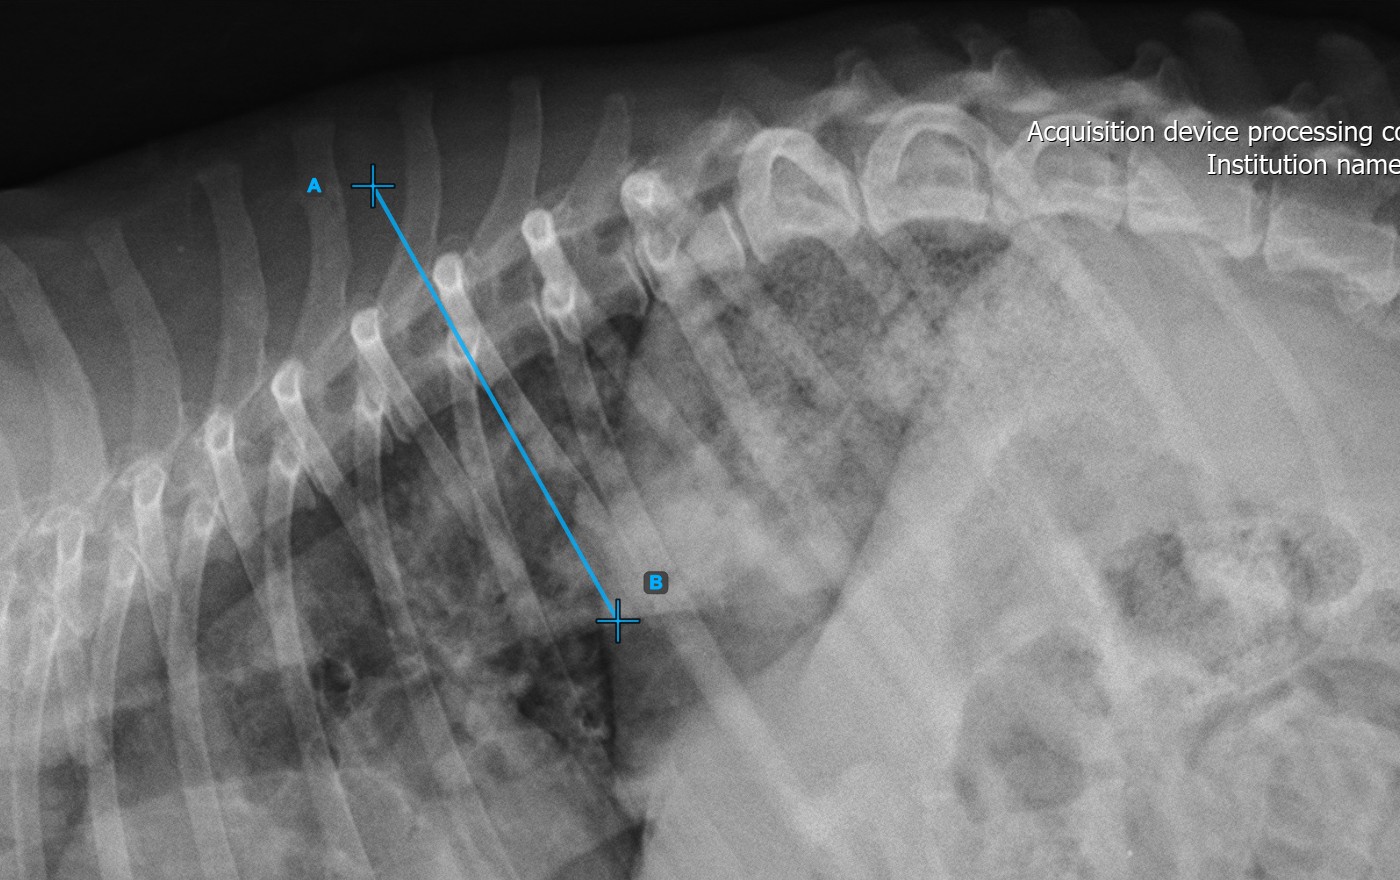

Mark the second vertebral line on the spine to calculate the deformity.

Identify the vertebral endplate at the opposite end of the largest spinal curve deformity. Place the start and end point of the second vertebral line precisely along the identified endplate. Adjust each point on the scene to better align the line with the endplate if needed.

The Cobb Angle measurement will be automatically calculated and completed once the two vertebral lines are placed, indicating the angle of spinal curviture in degrees.

The image below represents a typical placement of the second vertebral line.